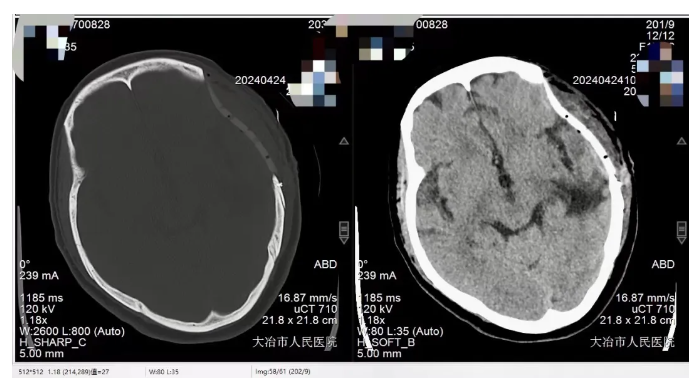

术后复查CT:

左侧头部皮下积液较术前明显消失,术后患侧外形还原度高,让患者重新找回“失去的”颅骨,找回自信。患者术后恢复良好,痊愈出院。